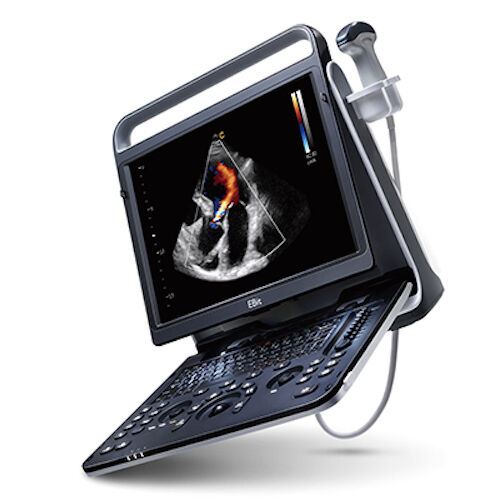

DIAGNOSTIC ULTRASOUND MACHINES FOR SALE

SonoScape S2 with one Trans vaginal Probe Used

Sale price$ 8,198.36